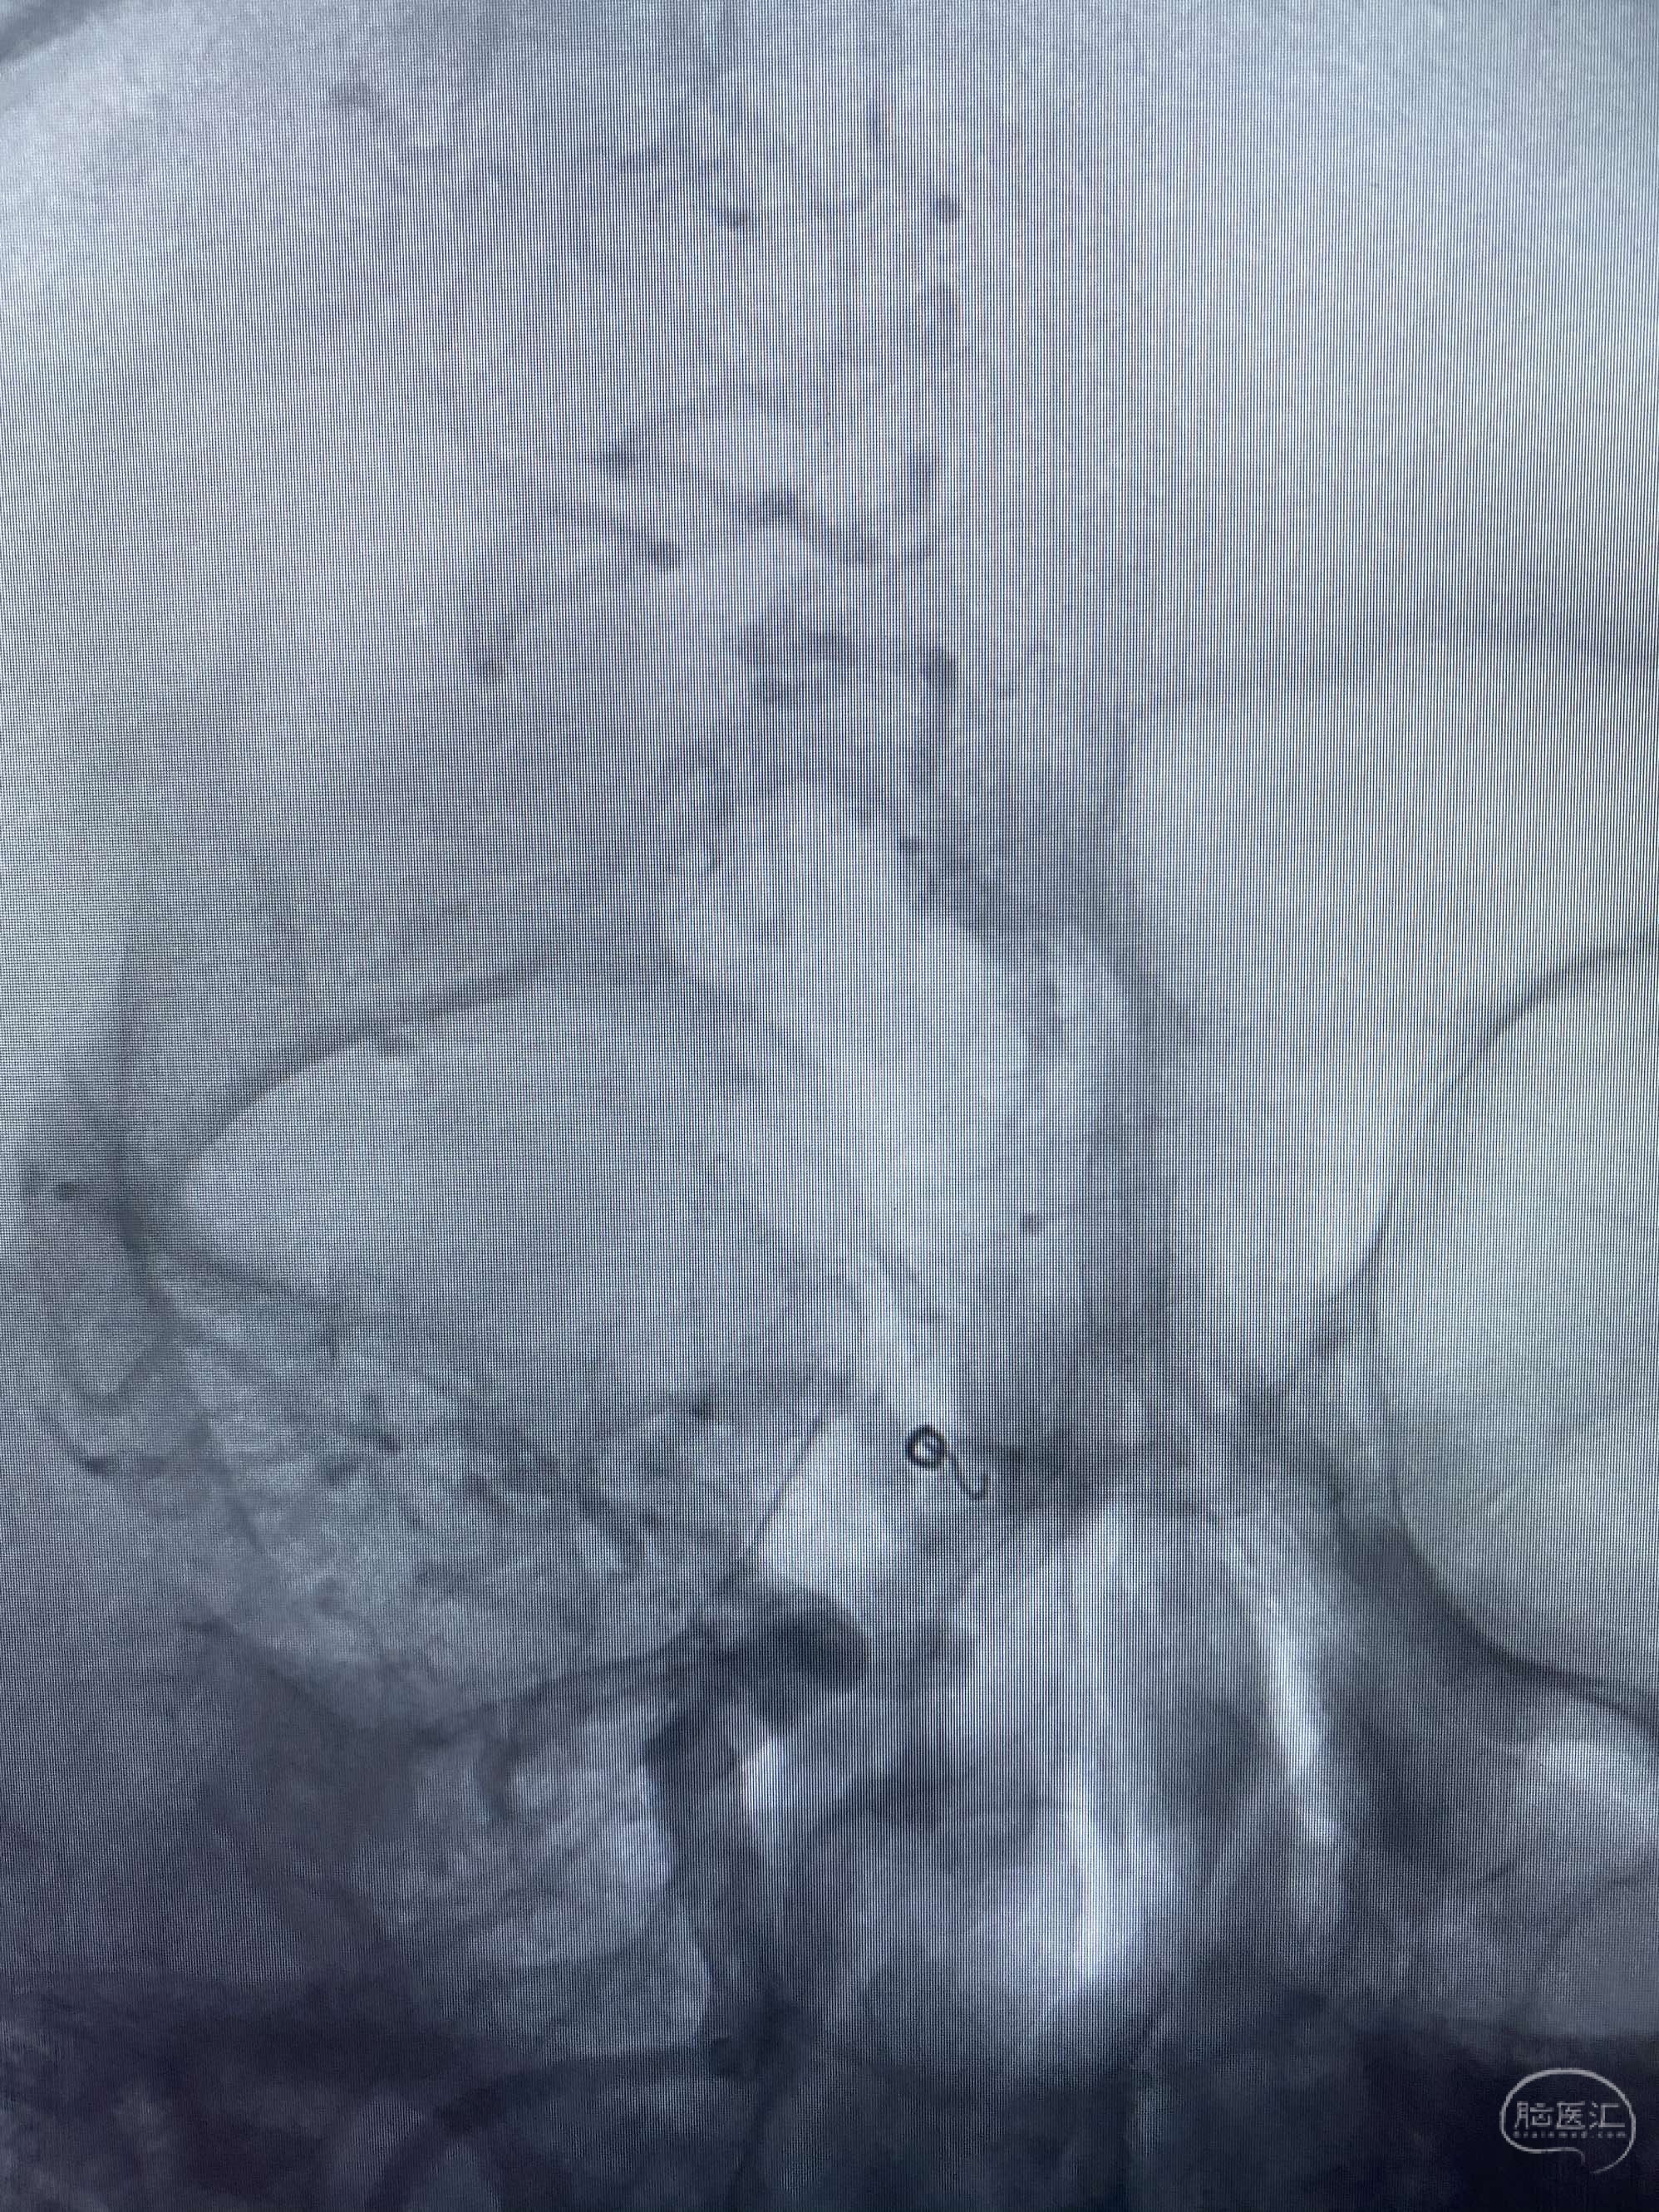

MLS,M79Y,sah,双侧MCA烟雾病,Heubner返动脉瘤,前交通段开窗,细支发出Heubner返动脉,瘤颈细长,瘤颈口比微导管细,弹簧圈2mmx3cm“隔山打牛”填塞治愈,Heubner返动脉保留。